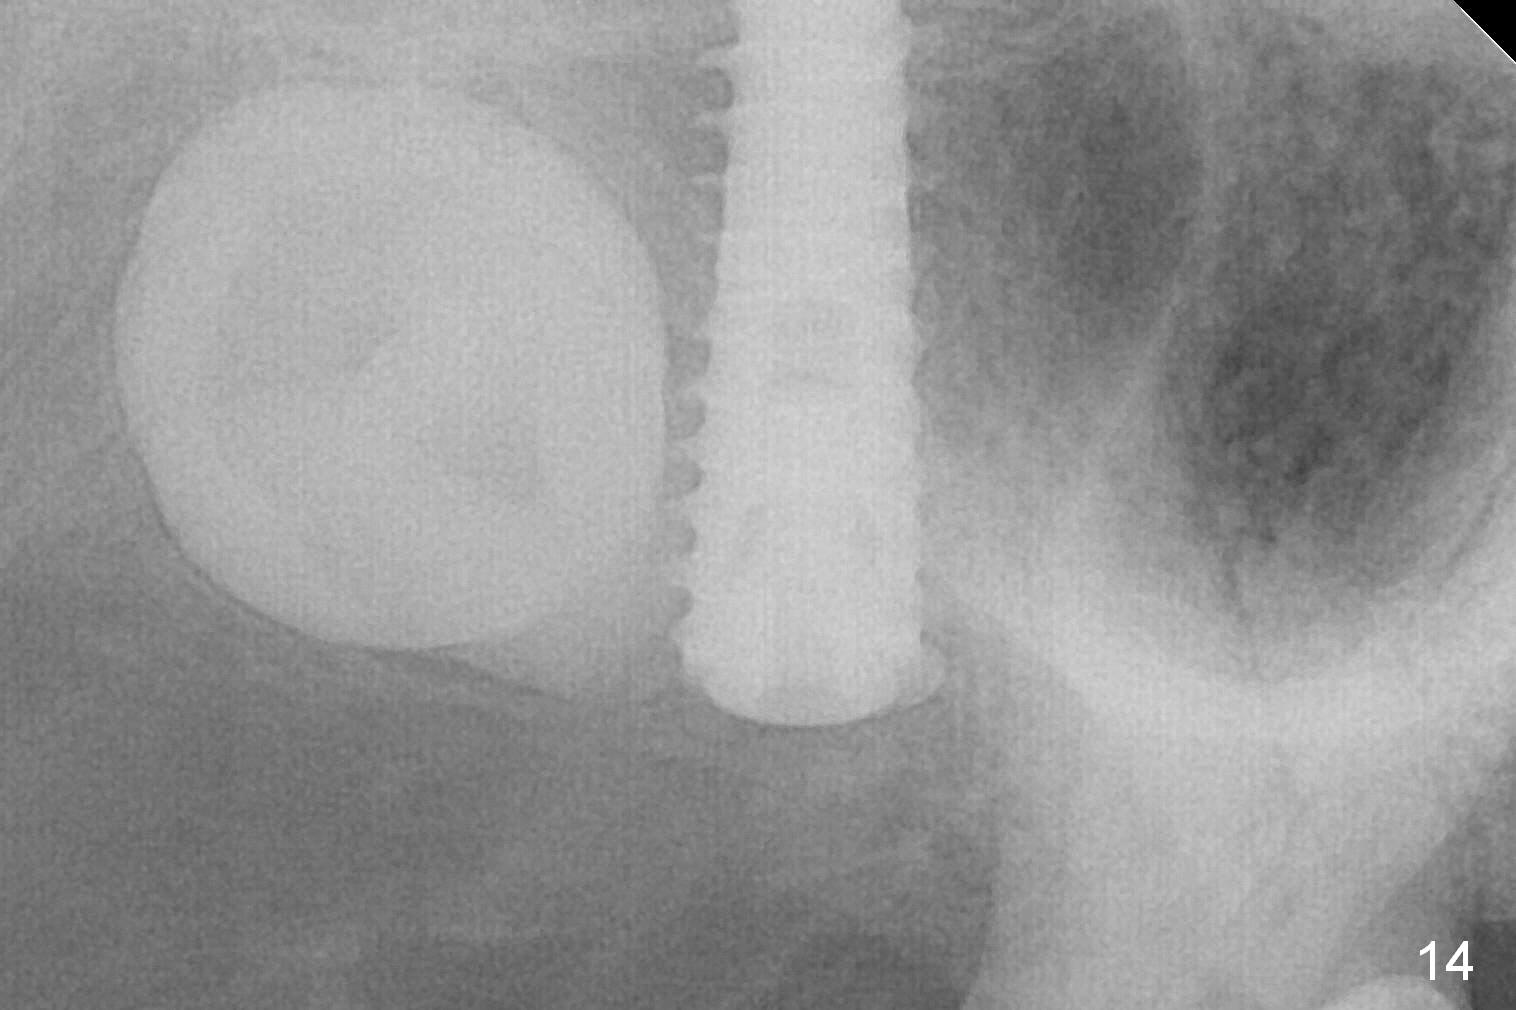

In fact, the implant is reversely torqued (1 month postop) and ~ 2 mm more coronally. It becomes looser. A healing screw is placed. With insertion of collagen plug, sutures are placed. Five days postop, the wound appears to be healing with sutures being dissolved. Four months later (5 months post placement), the patient returns asymptomatic. The wound heals. The implant appears to have osteointegrated and is at the crestal level (Fig.13,14). At uncover, the implant is found unstable; a healing abutment is placed. The implant is stable 8 months postop with apparently no gap between the bone and threads (Fig.15, as compared to Fig.13).